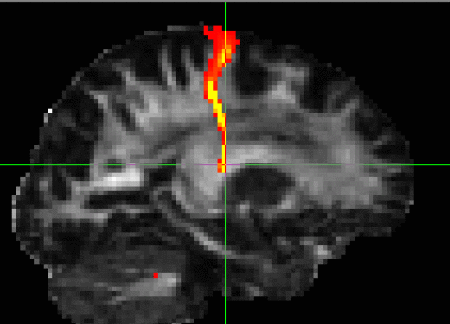

Vector images cannot be registered by simply applying a transformation (as calculated by, say, FLIRT) to every voxel's coordinates. The corresponding vectors have to be reoriented accordingly (see D. Alexander 2001, IEEE-TMI 20:1131-39). vecreg performs this operation for you. The image on the right shows the effect of applying vecreg (right) to the V1 image on the left, compared to simply applying voxelwise transformation (e.g. using applyxfm4D) to the vectors (centre).